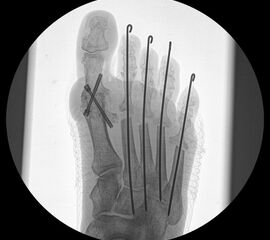

Abschließend erfolgt die temporäre K-Daht Fixation sämtlicher Kleinzehen in achsgerechter Stellung. Die Strecksehnen werden in Verlängerung vernäht.

Zum Lesen der Bildbeschreibung und zur Vollansicht bitte die Bilder anklicken.